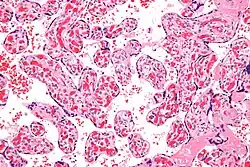

| Micrograph of a chorangiosis. H&E stain. | |

Chorangiosis is a placental pathology characterized by an abundance of blood vessels within the chorionic villi.

It is diagnosed by a microscopic examination of the placenta.

Commonly used criteria from Altshuler[2][3] are: "a minimum of 10 villi, each with 10 or more vascular channels, in 10 or more areas of 3 or more random, non-infarcted placental areas when using a ×10 ocular." The Altshuler criteria are not theoretically rigorous, as they do not define the area. Normal villi have up to five vascular channels.[3]